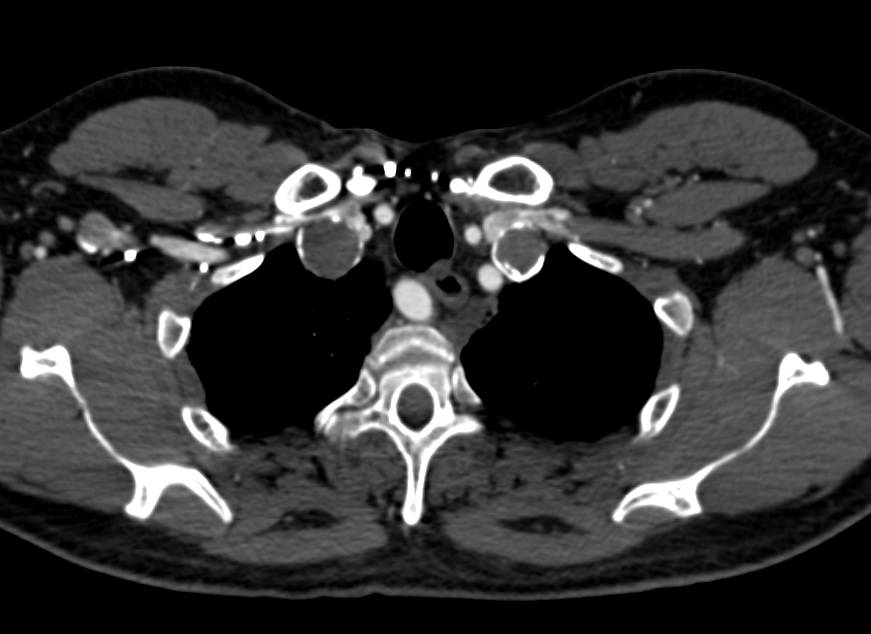

Left Axillary Artery Aneurysm